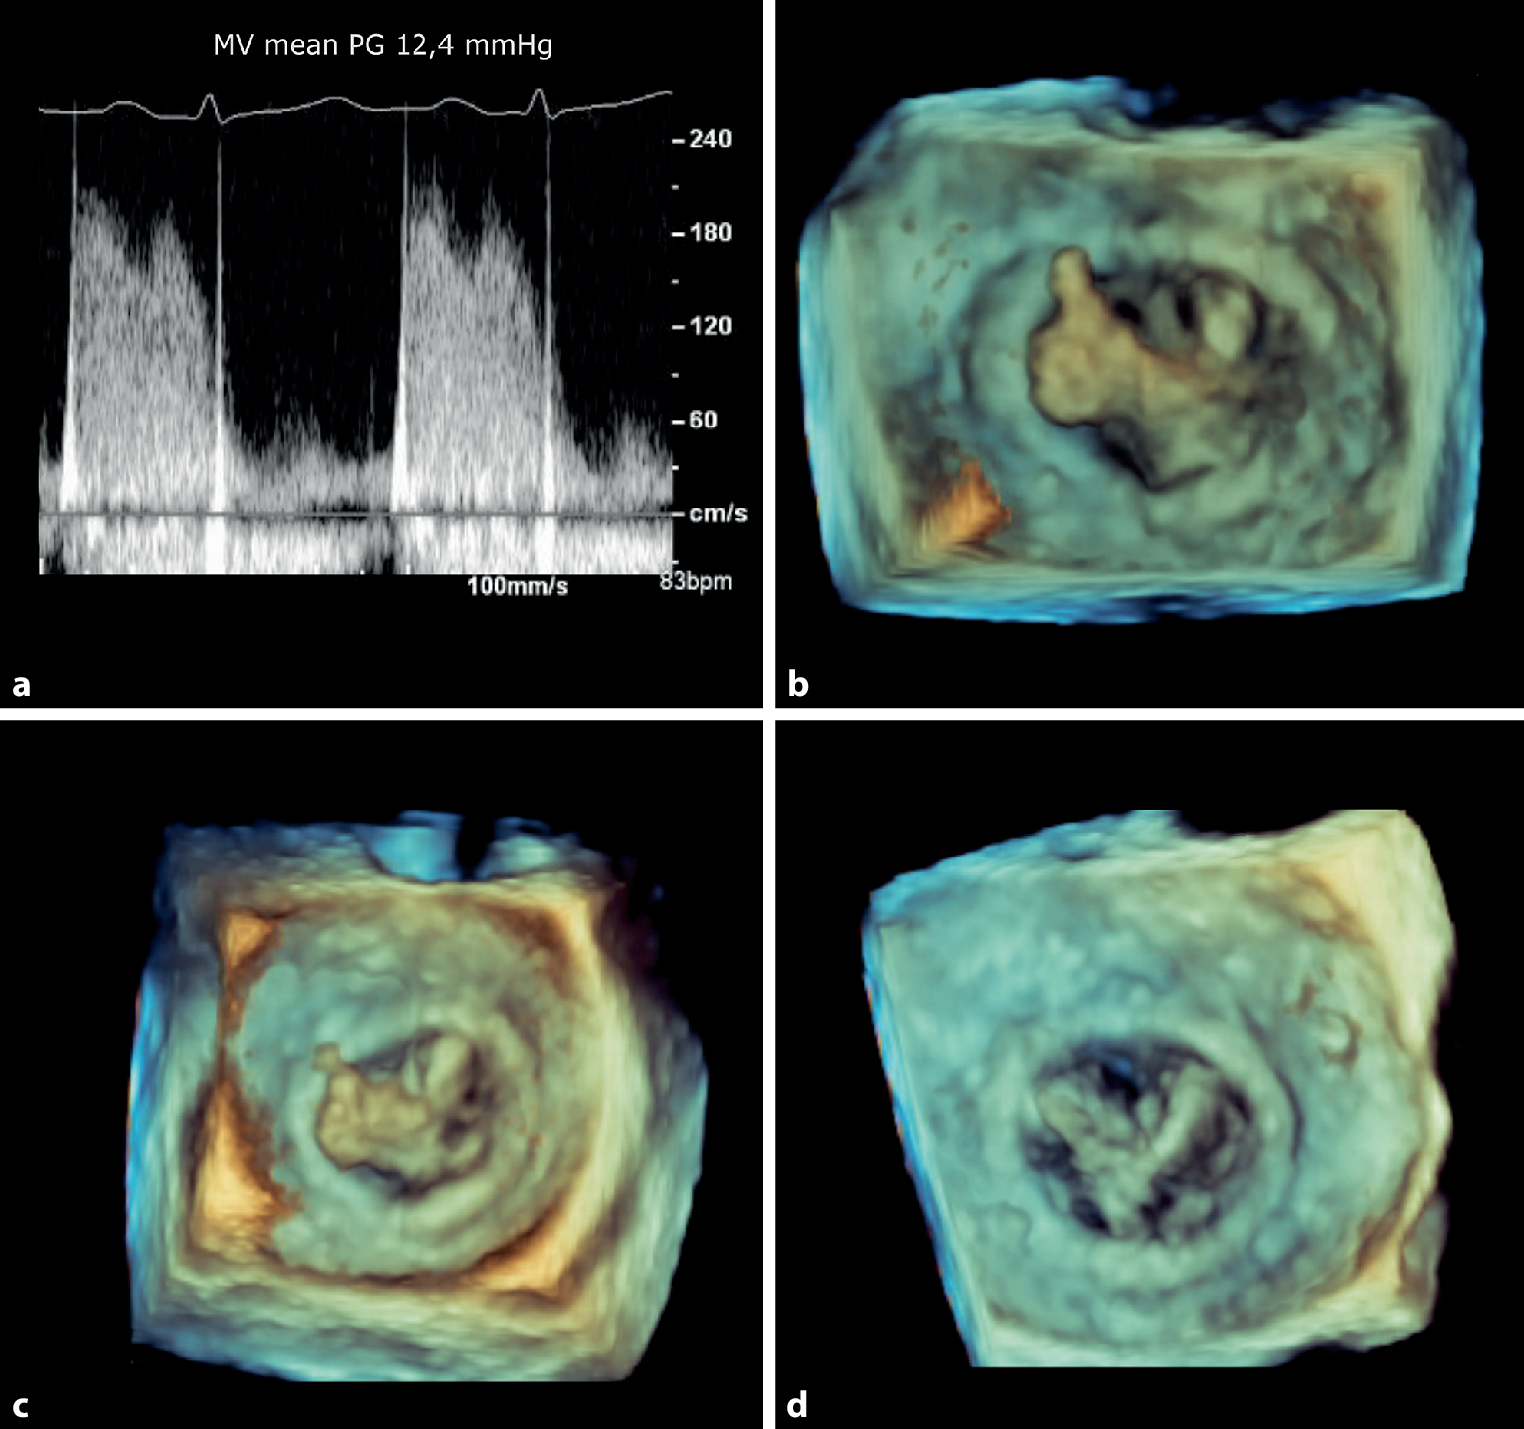

An 80-year-old woman presented with an ischaemic stroke one year after an uneventful bioprosthetic mitral valve replacement. Transthoracic echocardiography was of suboptimal image quality; however, Doppler interrogation of the mitral valve revealed a markedly elevated transvalvular gradient (Fig. 1a). Transoesophageal echocardiography showed a large, mobile mass, which was attached to the mitral bioprosthesis and mimicked a ‘thumbs-up sign’ (Fig. 1b; see also Video 1 in the Electronic Supplementary Material). As the patient was afebrile and both blood cultures and 18FDG PET/CT imaging were negative, bioprosthetic valve thrombosis (BPVT) was considered a more likely diagnosis than endocarditis. Patient was declined for surgery because of the high operative risk. Alternatively, treatment with a warfarin derivate was initiated. Follow-up echocardiography showed a gradual decrease of the echogenic structure size over time (Fig. 1c, d; see also Videos 2 and 3 in the Electronic Supplementary Material), with normalization of the transvalvular gradient.

Fig. 1

Bioprosthetic valve thrombosis a Elevated transvalvular gradient. b Echogenic mass attached to mitral bioprosthesis. c,d Gradual decrease of echogenic mass under oral anticoagulant therapy